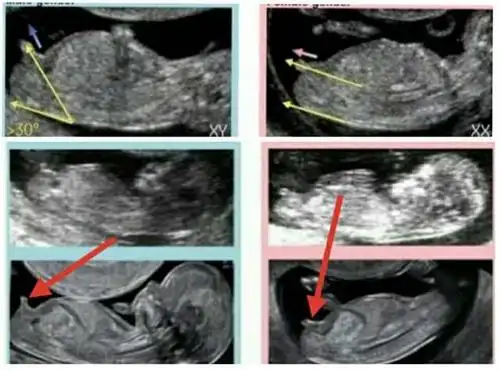

nt12周看见小丁丁了很神奇很准的nt看男女方法

双胎nt看男女